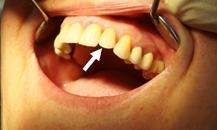

Diese

Einzelzahnkrone ist auf einem

Implantat

befestigt. Zustand 3 Jahre

nach Implantation